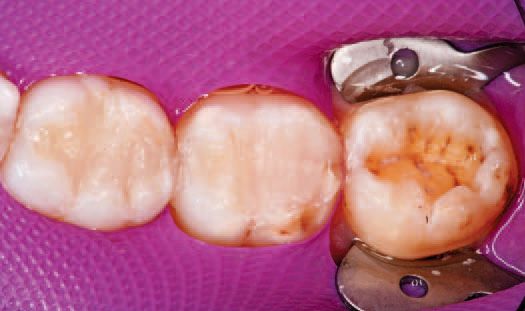

After inspecting the old amalgam restorations (Fig. 2), a rubber dam was then placed (Fig. 3). Next, using Sybron Dental’s Axis course diamond bur, KS3, the amalgam restorations and all damaged tooth structure were removed (Fig. 4).